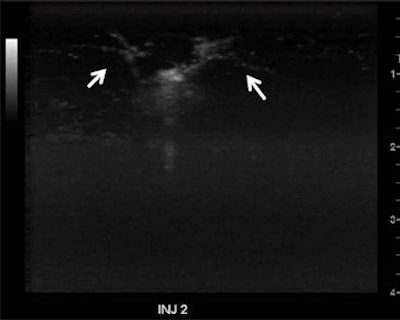

| Cumulative maximum intensity subharmonic breast ultrasound images show detailed tumor microvasculature (arrows). Image courtesy of the Journal of Ultrasound in Medicine. |